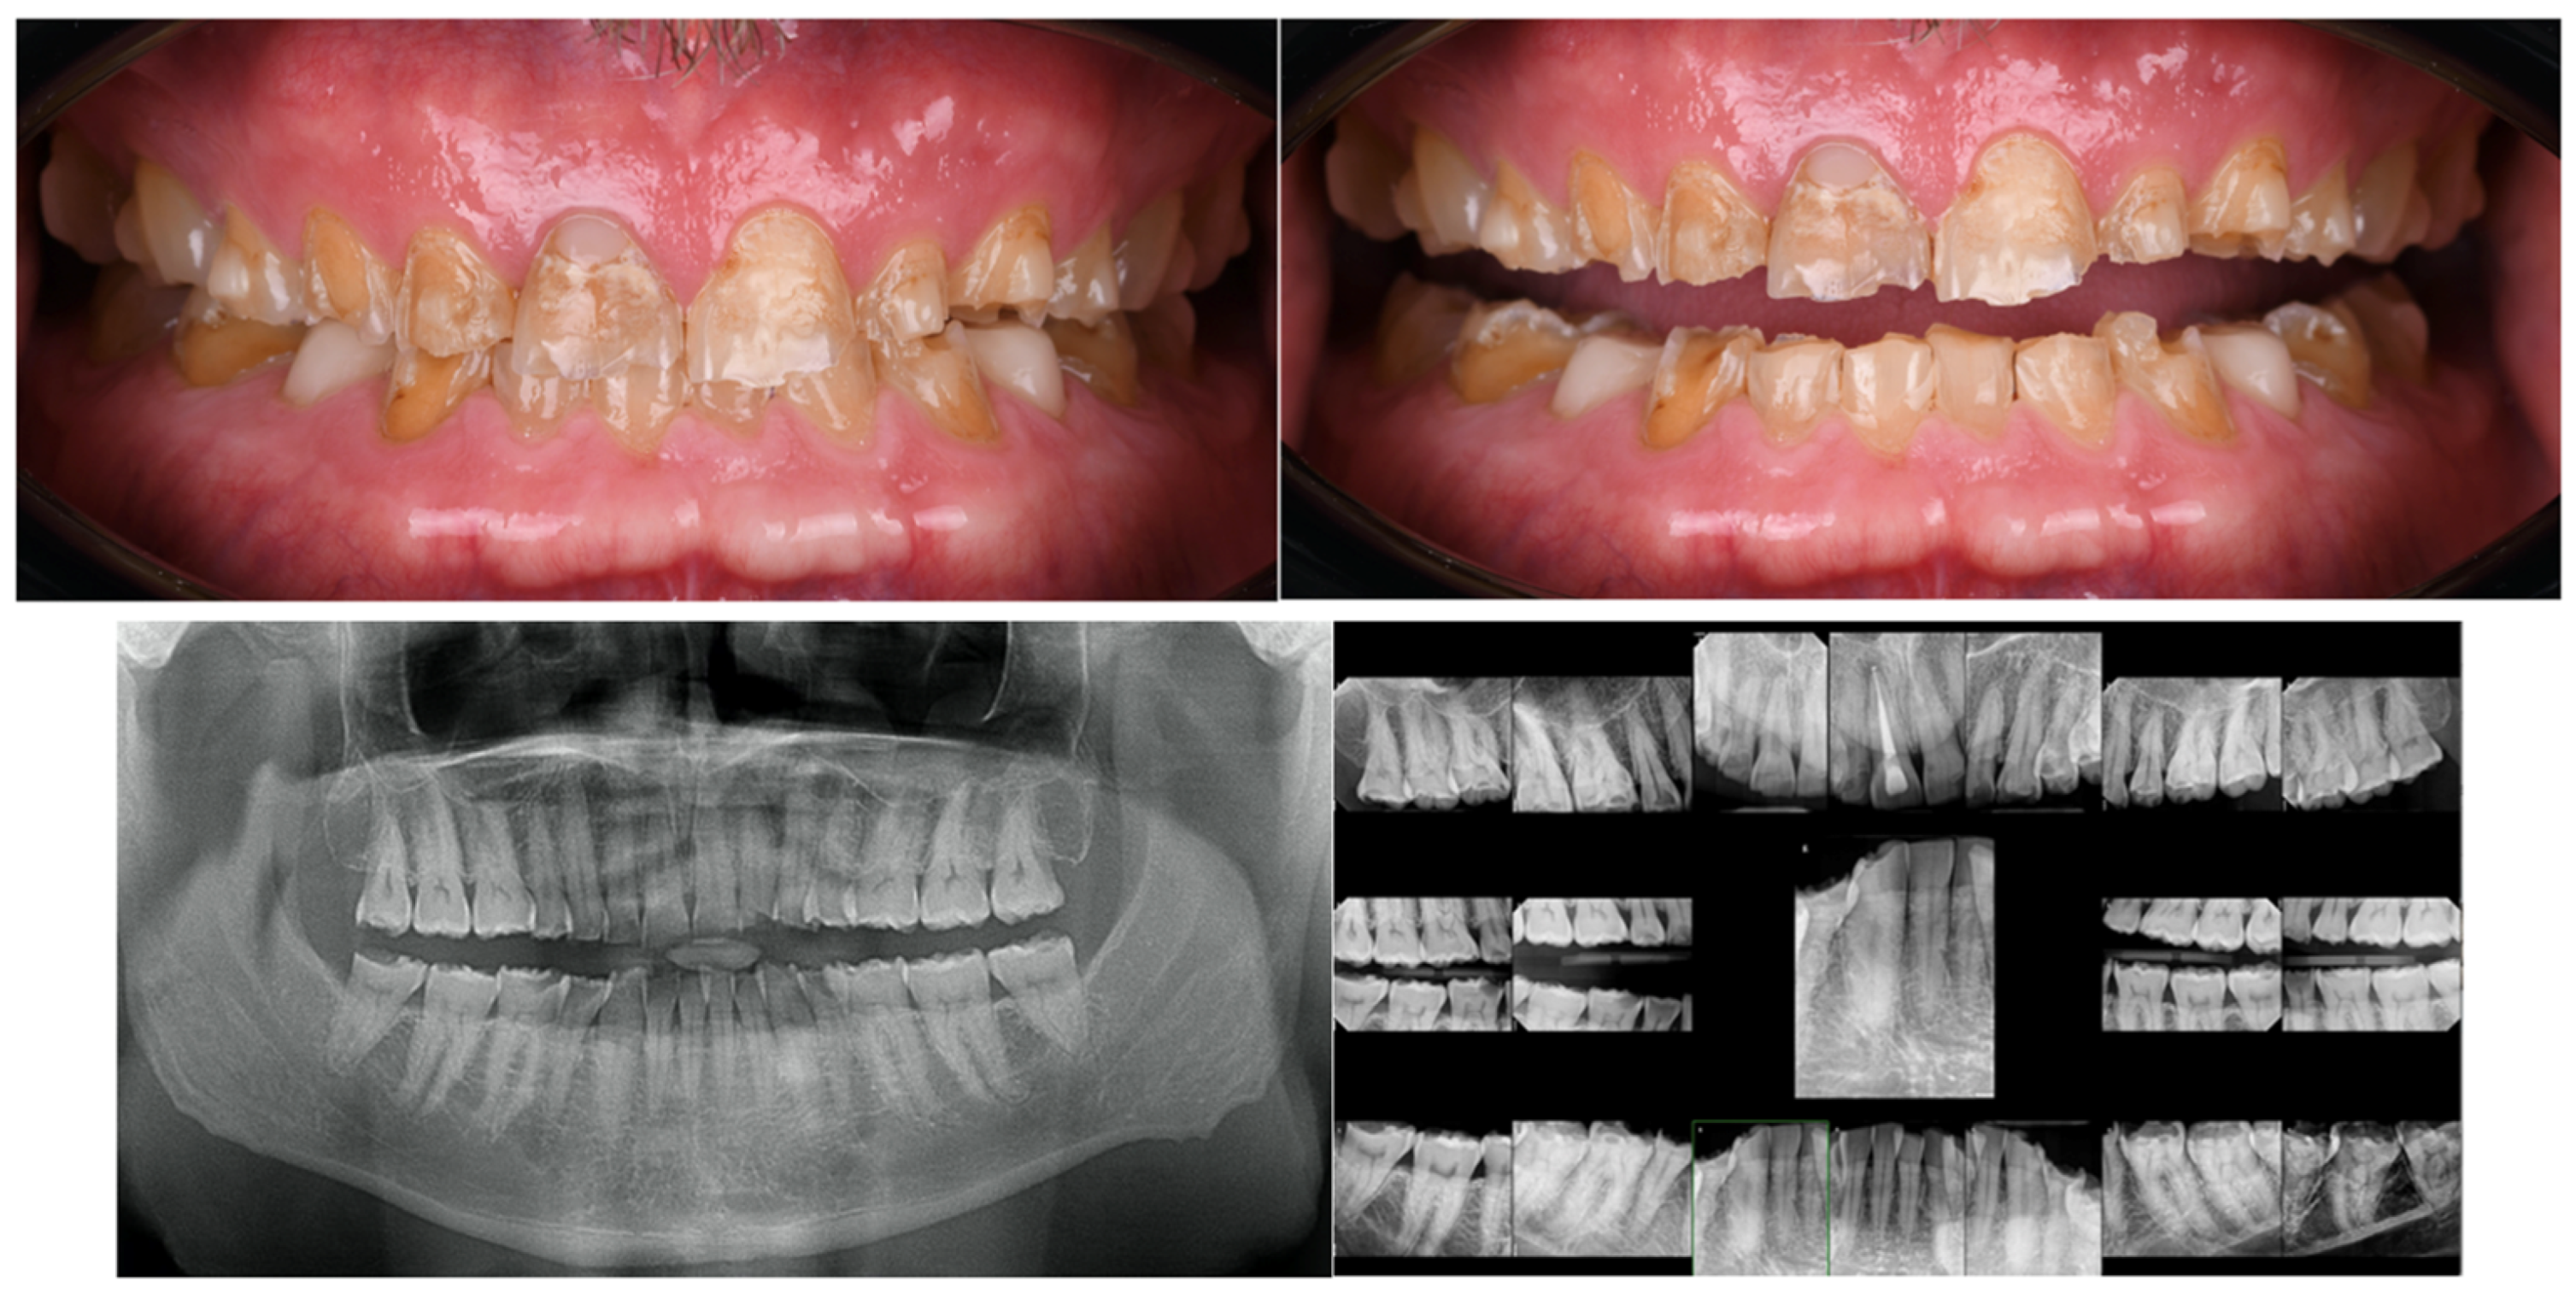

A Comprehensive Digital Workflow for Enhancing Dental Restorations in Severe Structural Wear

2. Materials and Methods